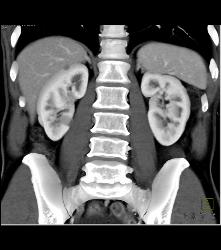

Gastric Adenocarcinoma With Celiac Nodes